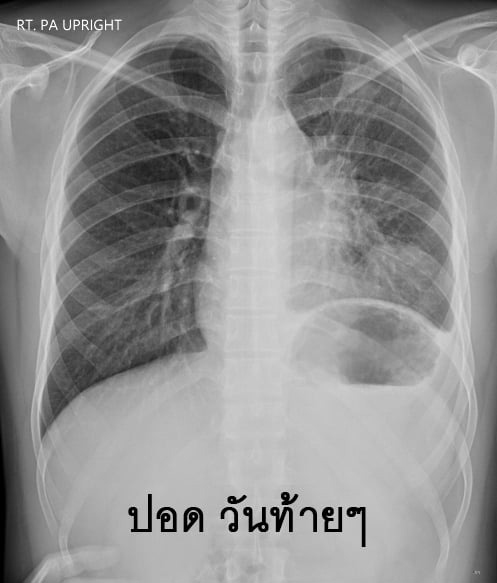

วันที่ 18 มิถุนายน 2563 เฟซบุ๊ก Chayanin Wisutthikul ได้แชร์ประสบการณ์ของเพื่อนคนหนึ่งที่ไอเป็นเลือด รักษากว่า 5 เดือน ตั้งแต่วันที่ 17 มกราคม 2563 เข้า-ออกโรงพยาบาล 3-4 แห่ง เบื้องต้นไปรักษาที่โรงพยาบาลที่ทำประกันสังคม แต่อาการไม่ดีขึ้น จึงไปรักษาที่คลินิกก็ได้ใบส่งตัวทำ CT SCAN เพราะมีการเอกซเรย์เบื้องต้น นอกจากจะเจอฝ้าที่ปอดแล้ว ยังเจอก้อนขาวกลางหน้าอก แพทย์ที่คลินิกกังวลว่าจะเป็นชิ้นเนื้อ จึงทำใบส่งตัวให้ไป CT SCAN ที่โรงพยาบาลประกันสังคม เพื่อช่วยเซฟค่าใช้จ่าย

แต่เมื่อเพื่อนไปถึงโรงพยาบาลประกันสังคม แพทย์และพยาบาลก็ไม่ได้สนใจใบส่งตัวทำ CT SCAN แต่ได้ให้ยาฆ่าเชื้อปอดอักเสบมา หลังจากผ่านไป 1 สัปดาห์ ก็ไม่พบว่ามีฝ้าที่ปอดแล้ว หมอก็บอกว่าไม่มียาให้แล้ว หายแล้ว กลับบ้านได้ เมื่อเพื่อนชี้ให้ดูที่หน้าจอเอกซเรย์ บอกว่าคลินิกที่ไปมาก่อนหน้านี้บอกว่าเป็นชิ้นเนื้อ แต่ทางหมอตอบกลับมาว่าเป็นเส้นเลือดใหญ่

ต่อมาเพื่อนก็กลับมาใช้ชีวิตปกติ เพราะหมอบอกว่าหายแล้ว แต่อาการไอไม่ดีขึ้นเลย แค่ไม่มีเลือดแล้ว เจ้านายจึงแนะนำแกมบังคับอีกรอบว่าให้ไป CT SCAN ที่ศูนย์แพทย์ซะ จะได้รู้ให้จบ ๆ ว่าเป็นอะไร เพื่อนก็เลยโทร. นัดแพทย์ที่คลินิกแพทย์อีกครั้ง และได้ทำ CT SCAN ในวันที่ 24 มีนาคม 2563 ผลออกมาว่า จุดขาว ๆ ที่กลางหน้าอกคือเนื้องอก ที่ตอนนี้มีขนาดความยาว 9x8x7 cm (ขนาดประมาณเท่ากำปั้น) หลังจากนั้นแพทย์ก็เขียนใบส่งตัวให้ไปรักษาที่โรงพยาบาลประกันสังคม (เพื่อนทำเรื่องเปลี่ยนโรงพยาบาลประกันสังคมแล้ว)

24 พฤษภาคม 2563 วันฟังผล สรุปว่าเป็นเนื้อไม่ดี ตอนนี้ได้ทำการส่งตัวไปรักษาตัวต่อที่โรงพยาบาลอีกแห่งหนึ่ง เพื่อดูแนวทางในการรักษาต่อไป

10 มิถุนายน 2563 เวลา 8 โมงเช้า ไปเอาใบส่งตัว แล้วเดินทางต่อไปที่โรงพยาบาล ปรากฏว่ายังทำอะไรไม่ได้อีก เพราะว่าเอกสารส่งตัวไม่ครบ ยังดำเนินการไม่ได้ จนกระทั่งสุดท้ายได้ความจากแพทย์ในวันที่ 17 มิถุนายน 2563 ว่า "คุณเป็นมะเร็งต่อมน้ำเหลืองนะ"